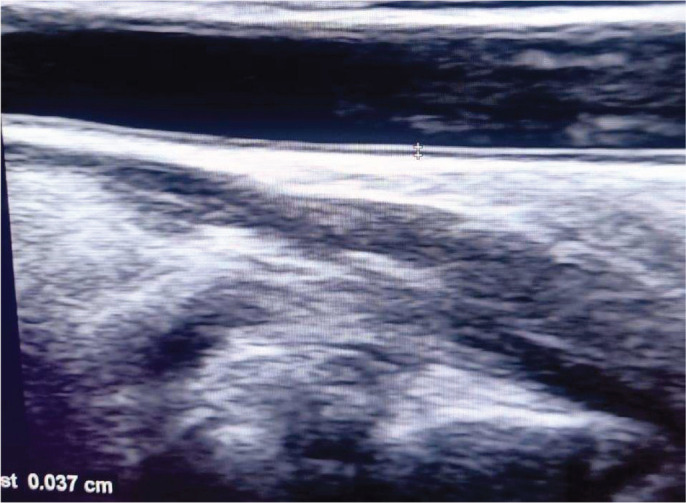

Background and aim: The aim of the current study is to assess the relation between carotid intima-media thickness (CIMT) measurements, renal Doppler resistive index (RI) and serum levels of interleukin-13 (IL-13) and annexin-V (An-V) in children with idiopathic nephrotic syndrome (INS).

Materials and methods: The present case-control study was conducted on 60 children with INS and 60 age- and sex-matched healthy children. All participants were subjected to evaluation of serum levels of IL-13 and An-V and ultrasound Doppler measurement of CIMT and renal RI.

Results: Patients expressed significantly higher An-V (5.9 ± 2.6 vs. 2.1 ± 0.8 ng/mL, p<0.001) and IL-13 (19.2 ± 7.6 vs. 3.4 ± 1.4 ng/L) levels when compared with healthy counterparts. Moreover, it was shown that patients had significantly higher CIMT (0.49 ± 0.06 vs. 0.35 ± 0.03, p<0.001) as compared to controls. No significant differences were noted between the studied groups regarding right or left RIs. Correlation analysis identified significant direct correlation between serum An-V levels and albumin/creatinine ratio (ACR) (r = 0.55), cholesterol (r = 0.48), triglycerides (r = 0.36), IL-13 (r = 0.92) and CIMT (r = 0.53). Similar correlations could be found between serum IL-13 levels and CIMT measurements and the corresponding parameters.